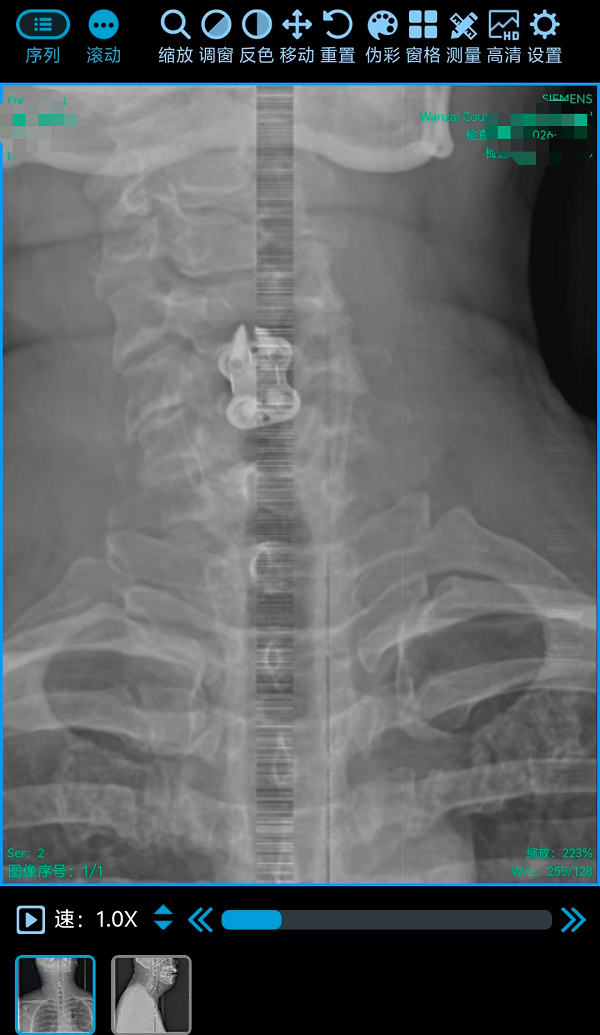

2. 为颈椎间盘巨大突出致肢体不全瘫患者行颈椎前路椎间盘切除融合内固定术(ACDF)(四级手术),该术式通过颈部前方的天然解剖间隙到达病变节段,在彻底解除脊髓和神经根压迫的同时,重建了颈椎的生理曲度和稳定性。手术团队凭借丰富的经验和精细的操作,在方寸之间精准完成了减压、植骨与内固定,有效避免了重要神经血管的损伤。